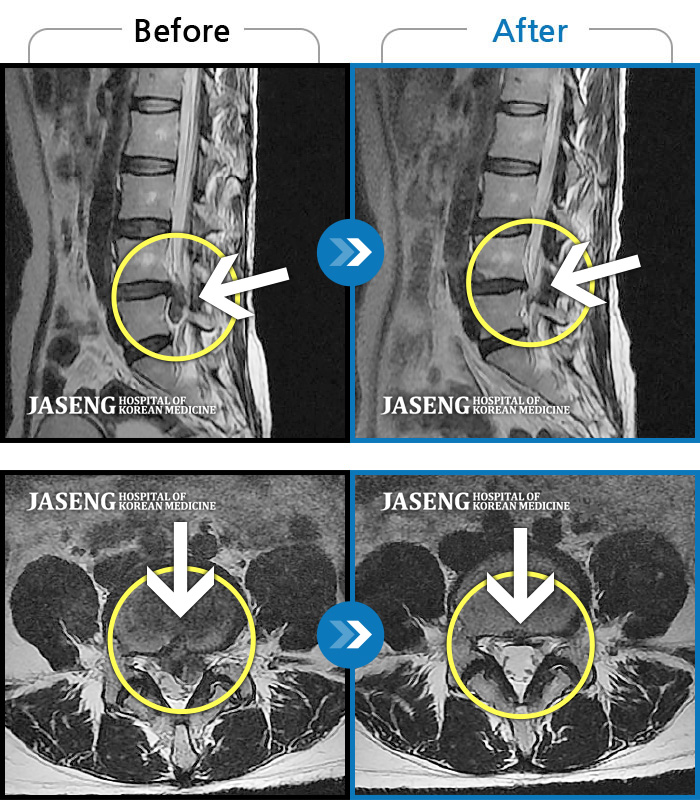

일산 · 배영현 원장

허리, 좌측 골반, 좌측 다리 통증 및 저림이 심해서 정상적인 일상생활이 힘든 상태

촬영시기

2021.10.04 ~ 2022.11.18

2022.12.02